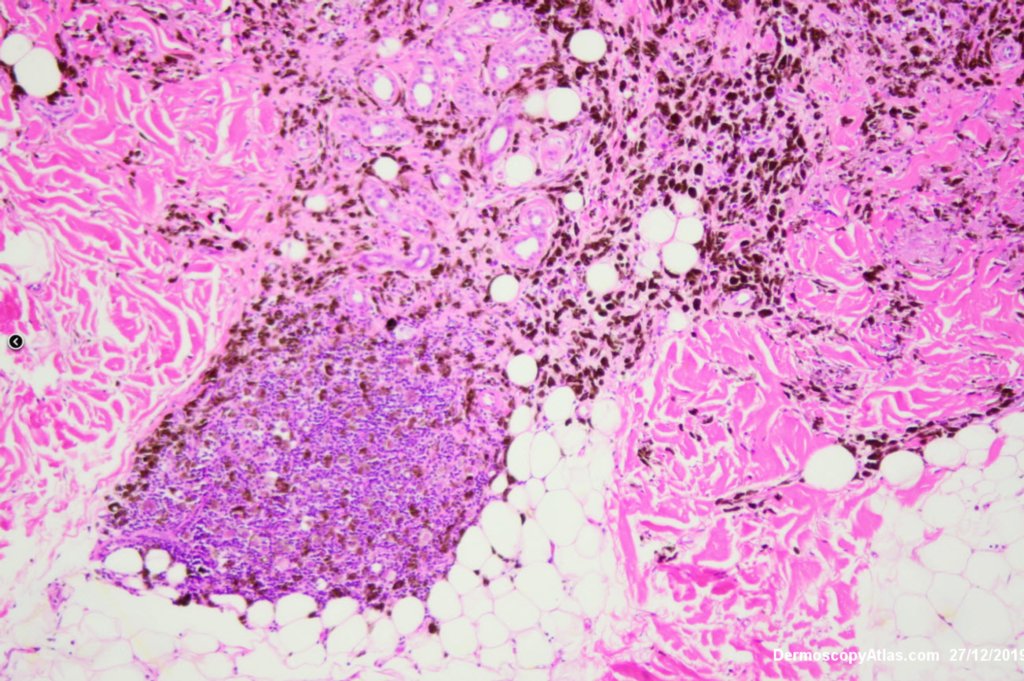

Image Number #3527 (Melanoma metastases)

Diagnosis: Melanoma metastases

Description: Background brown lesion with blue macules and papules developing

This elderly man had a preceeding lentigo maligna but subsequently developed in transit metastases as shown by the blue macules and papules on his cheek. He was treated with Keytruda. PET scan was negative for spread elsewhere.

It is important to treat lentigo maligna early to stop a situation like this from developing.